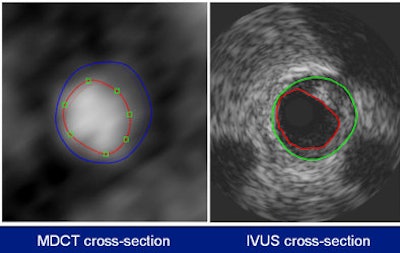

In a direct comparison between multidetector-row CT (MDCT) and intravascular ultrasound (IVUS), CT was nearly as accurate for detecting both calcified and noncalcified coronary artery plaque, according to a Dutch study presented at the recent RSNA meeting in Chicago.

The MDCT analysis included the normal MDCT image, the MDCT gradient image, and the longitudinal vessel view. Quantitative parameters were determined per 1-mm cross-section and included the lumen area, the vessel area, plaque area, and maximum wall thickness. Plaque was deemed to be present when the wall thickness exceeded 0.5 mm. Regions of interest (ROI) plaque volumes were calculated as the sum of plaque volumes of all the ROI cross-sections. All images courtesy of Dr. Stella-Lida Papadopoulou.Both IVUS (44-mHz catheter) and 64-detector-row MDCT were performed in 32 symptomatic patients. The MDCT and IVUS datasets of 44 coronary arteries were coregistered using a newly developed and validated fusion technique that derived quantitative parameters from both imaging modalities using a stepwise approach.

"For analysis of the results, several parameters were compared by section, including lumen area, vessel area, plaque area (vessel area minus lumen area), and maximum wall thickness, defined as the distance between the lumen and the vessel wall," Papadopoulou said. "We considered plaque to be present when the maximum wall thickness was above 0.5 mm." This is criterion commonly used for IVUS but it has not been previously used for CT.